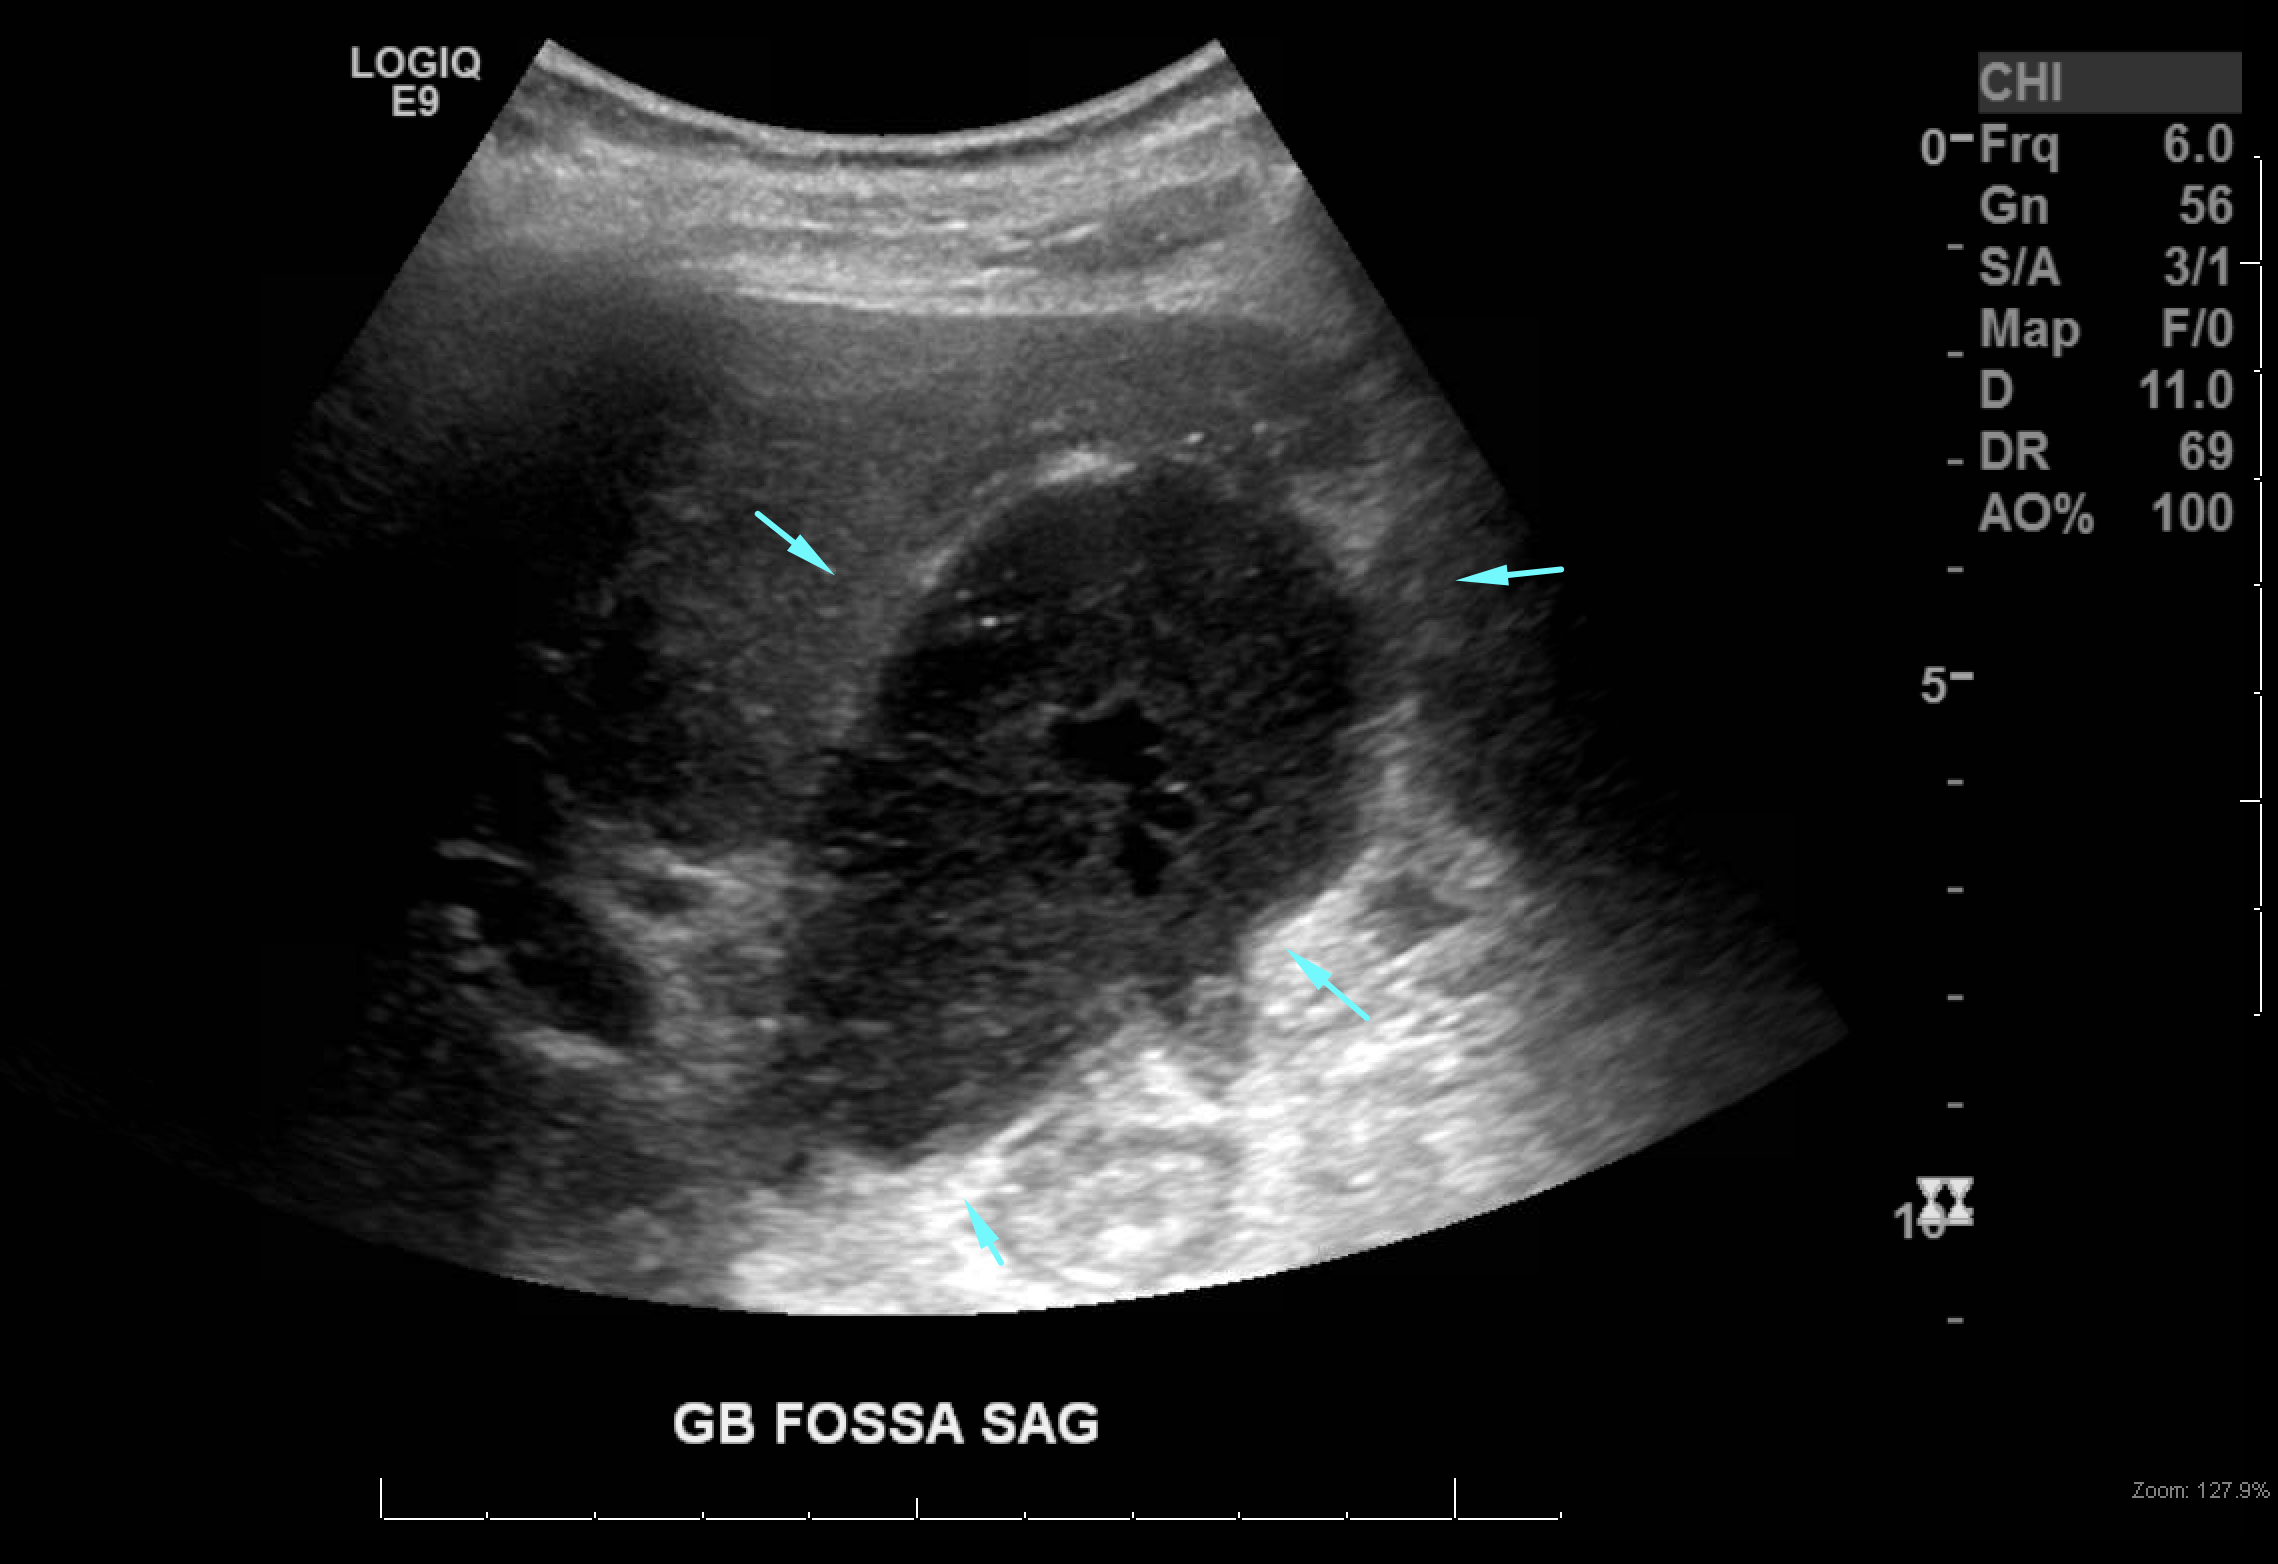

Age: 84

Sex: Male

Indication: Left-sided chest pain, recent cholecystectomy

Radiotracer: Tc99m mebrofenin (an iminodiacetic acid analog)

Sample ReportPositive for biliary leak, which is drained by the existing surgical drains.

No evidence of intra-abdominal bile collections.

No evidence of common bile duct obstruction.